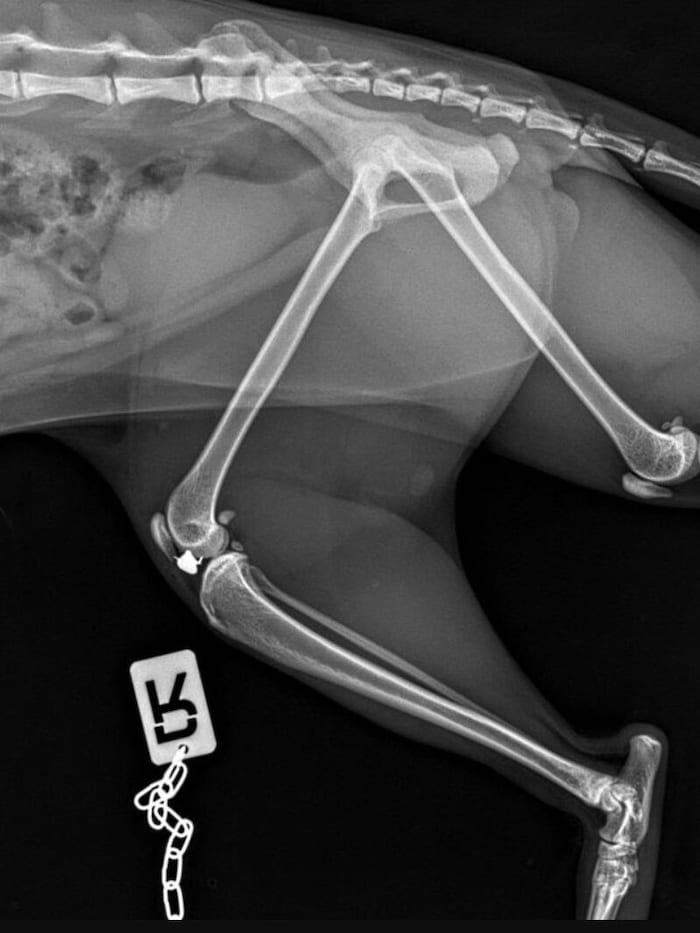

Die Erstuntersuchung im Tiermedizinischen Zentrum Teesdorf (NÖ) brachte Gewissheit. Eine frische Wunde in der Kniefalte, ein Röntgenbild mit metallischem Fremdkörper. „Luna“ wurde noch am selben Tag notoperiert. Die Chirurgen fanden ein kleinkalibriges Projektil, vermutlich aus einer Luftdruckwaffe, tief im Knie der Katze.